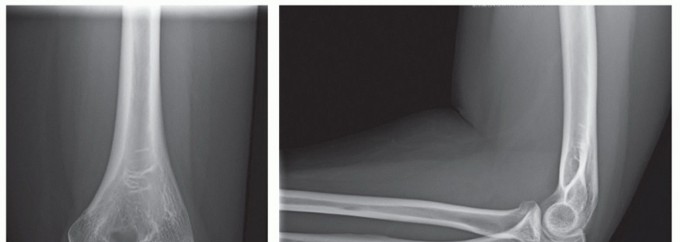

Axial loading may also rupture the interosseous membrane causing longitudinal radioulnar instability with dislocation of the distal radioulnar joint (DRUJ) (Essex-Lopresti fracture). An impacted radial neck or depressed radial head fracture should be highly suspicious of a concomitant interosseous membrane and DRUJ injury (FIG 4).

FIG 4 • AP x-ray showing a depressed articular fracture with impaction at the radial neck. This fracture pattern is highly suspicious for an Essex-Lopresti fracture. Radial head replacement is recommended. If ORIF is performed, the DRUJ should be stabilized to prevent instability.

FIG 5 • A,B. AP and lateral x-ray showing a type II Monteggia fracture—posterior dislocation of radial head (or fracture) and proximal ulnar fracture with posterior angulation. C. CT scan clearly showing impaction fracture of the radial head that may not be appreciable on x-ray.*